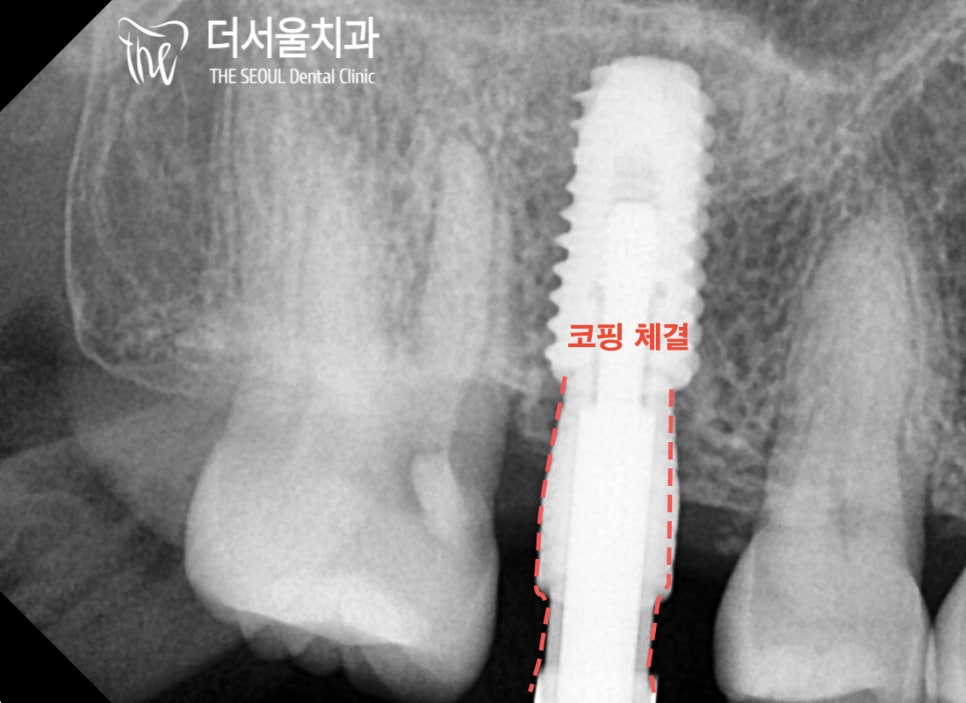

픽스처 위에

코핑이라는 특수한 기구를 체결하고

치근단 촬영으로 잘 들어갔는지 확인하게 되는데요.

해당 사진을 보면

알맞게 체결된 것을 볼 수 있네요^^